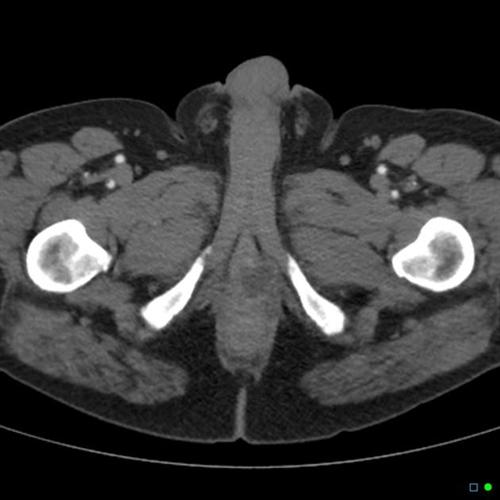

相关图片